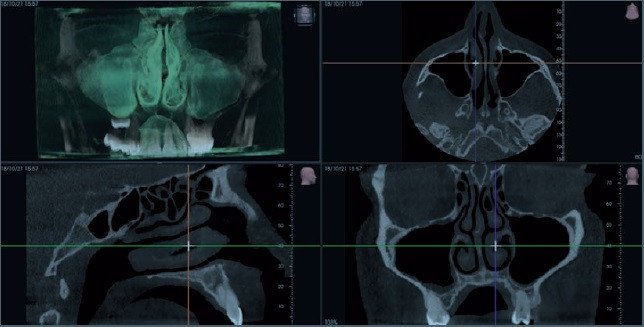

CORE 1000 biedt een breed scala aan volumetrische groottes, elk ontworpen voor specifieke behoeften. Met speciale FOV's, filters, geoptimaliseerde protocollen en Scout View halen gebruikers het maximale uit hun apparatuur en genieten van steeds betere prestaties.

Met de zeer flexibele geavanceerde oplossingen van CORE kan men zelfs de de meest complexe morfologieën onderzoeken, zelfs de kleinste anatomische details vastleggen en mogelijke positioneringsfouten van de patiënt corrigeren.

·         Segmentatie van 3D anatomische structuren

·         Anatomische en pathologische analyse voor 2D intraorale en panoramische scans